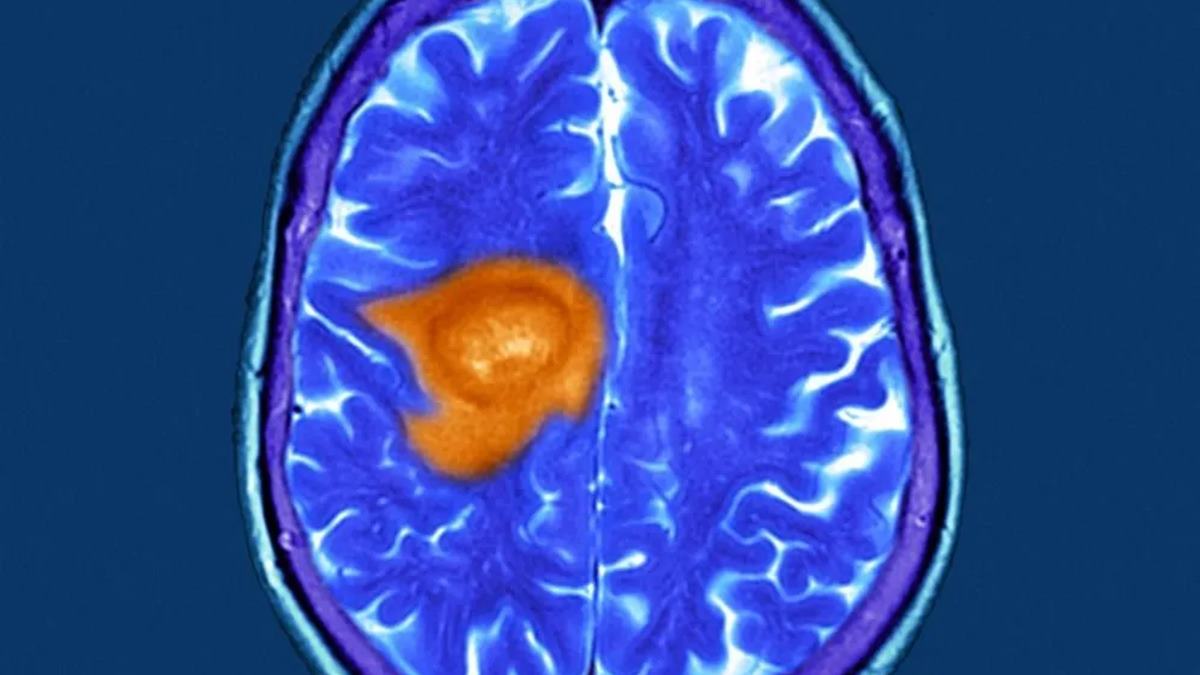

A glioblasztóma napjaink egyik legfélelmetesebb és legagresszívabb agydaganat típusa.